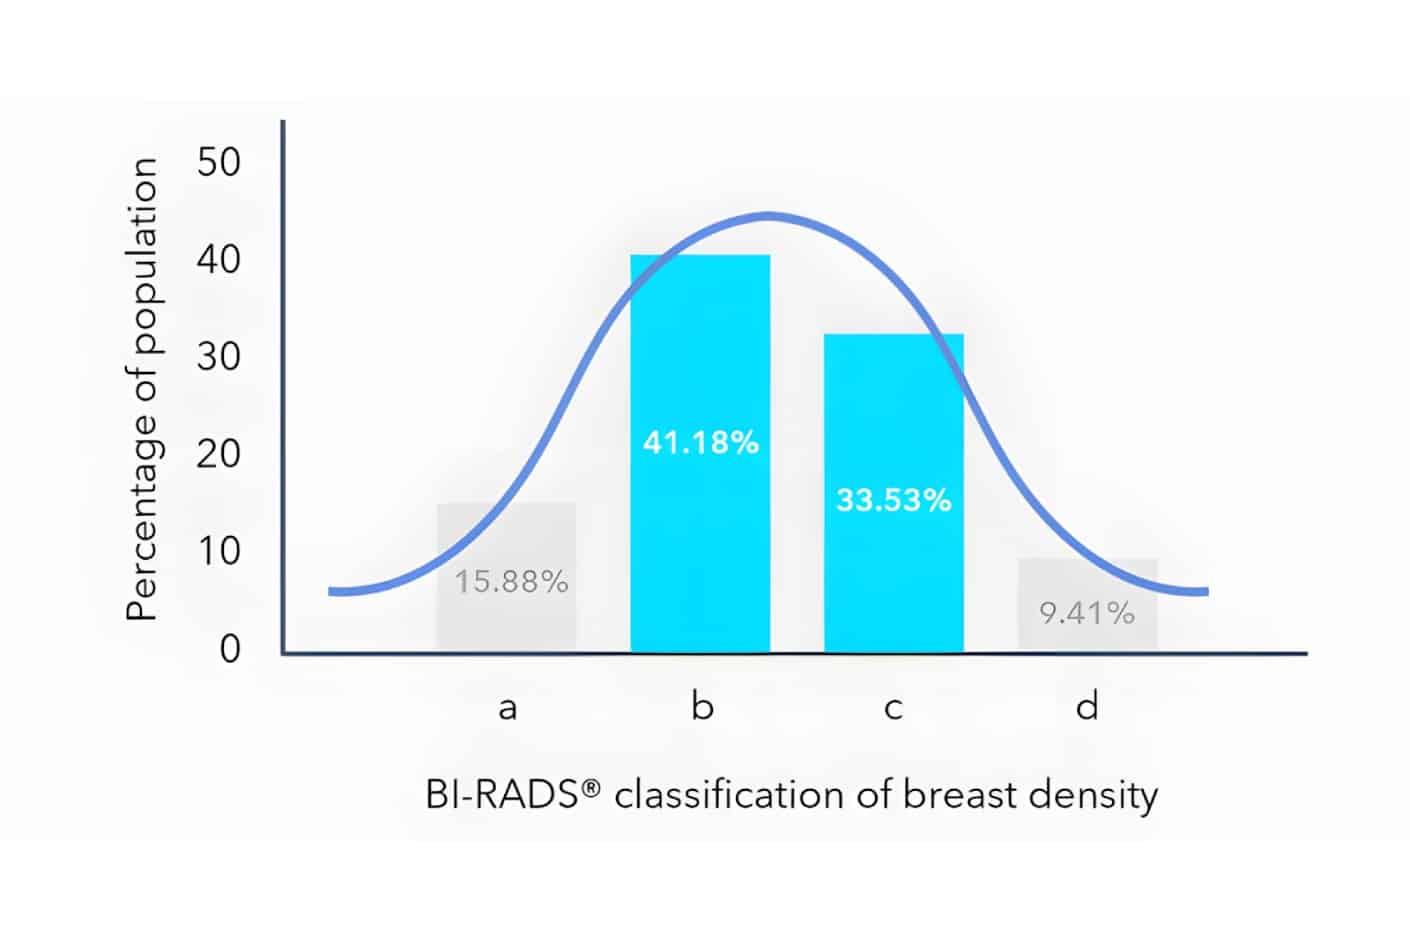

Volpara’s FDA-cleared TruDensity™ algorithm powers Scorecard, a breast density assessment software that delivers consistent, volumetric insights. It provides clinicians with consistent, objective data to support earlier cancer detection and supplemental imaging recommendations.

By providing an objective density score, we help clinicians determine when supplemental screening methods may be necessary, ensuring that high-risk patients receive the right care at the right time.

Scorecard is a trusted standard for breast density analysis, used in over 4,800 hospitals and backed by 400+ studies.